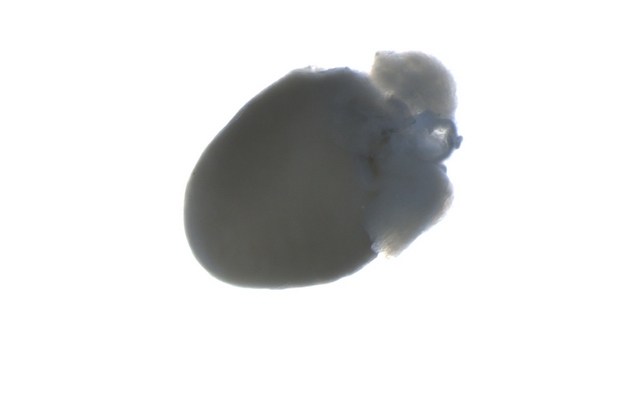

MZX81显微镜以其出色的明场和荧光成像能力,为科研人员提供了清晰锐利的观察体验。在明场模式下,心脏组织的细微结构一览无余,细胞轮廓分明,为后续的深入分析奠定了坚实基础。而切换到荧光模式时,MZX81又能够精准捕捉荧光标记信号

小鼠心脏